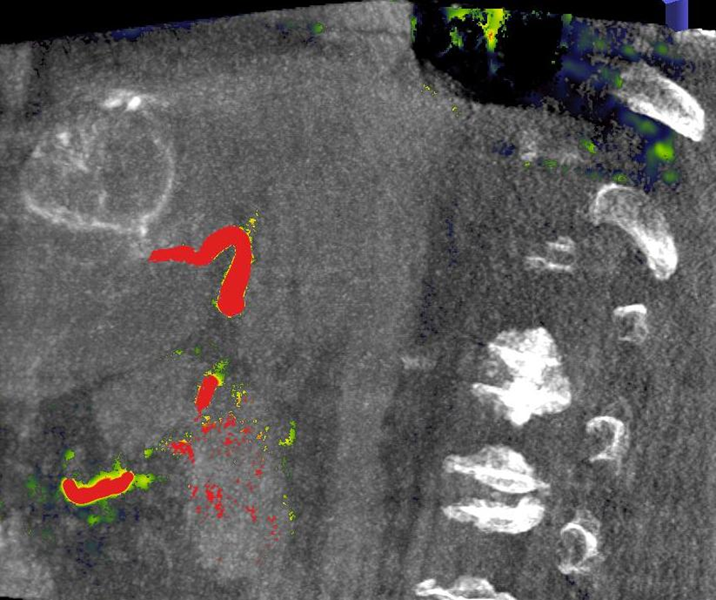

Thermoablation von Lungentumoren

Die minimalinvasive Thermoablation ist auch eine Therapieoption für Lungentumore. Damit ein Lungentumor mit diesem Verfahren effektiv und sicher behandelt werden kann, sollten bestimmte Bedingungen (wie Größe, Anzahl und Lage) erfüllt sein. Ob diese Voraussetzungen gegeben sind, wird das Vorgehen vor der Therapie mit Kollegen aller für diese Fragestellung relevanten Fachdisziplinen besprochen.

Abbildung: Bei der perkutanen Thermoablation von Lungentumoren werden spezielle Applikatoren unter CT-Bildgebung in den Zieltumor eingebracht. Durch Hitze wird der Tumor dann zerstört.